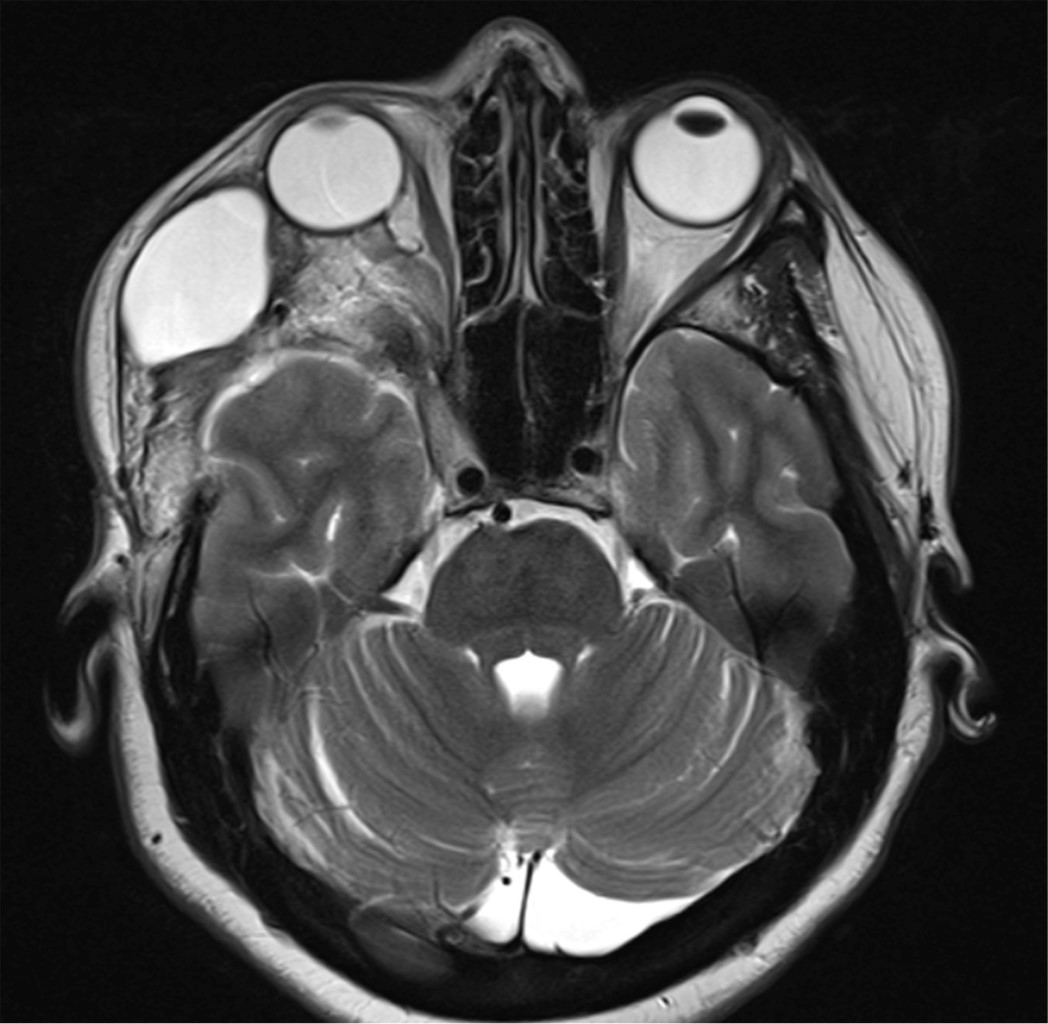

En la resonancia magnética simple y contrastada de encéfalo se observa tumoración extraaxial dependiente del ala menor del esfenoides del lado derecho con extensión en placa a techo orbitario y fosa media, componente tumoral intraorbitario extraconal que desplaza estructuras intraoculares, compatible con meningioma esfeno-orbitario derecho (Figura 1).

Figura 1